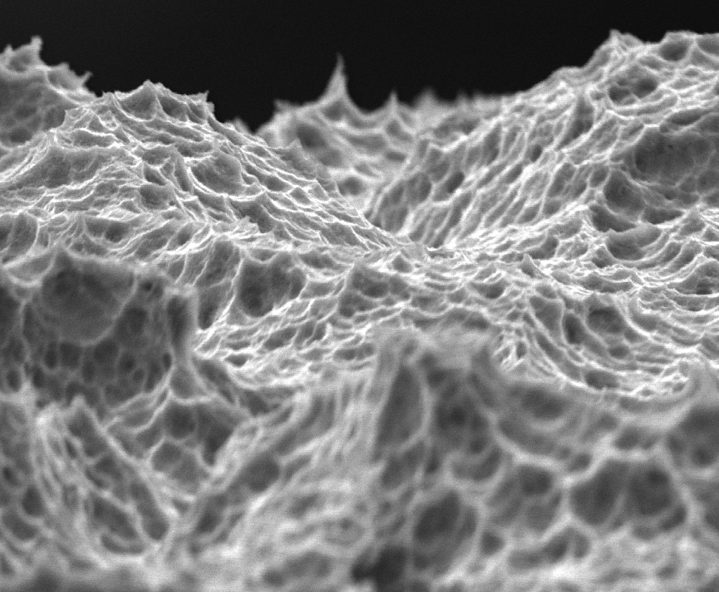

Topografía de superficie híbrida contemporánea (gruesa y fina)

Micrométrica gruesa 2000 X

Superficie micrométrica gruesa:

En el cuerpo del implante existe una transición hacia una superficie más rugosa que favorece la oseointegración. Las rugosidades micrométricas gruesas en esta sección son mayores a 10 micras.